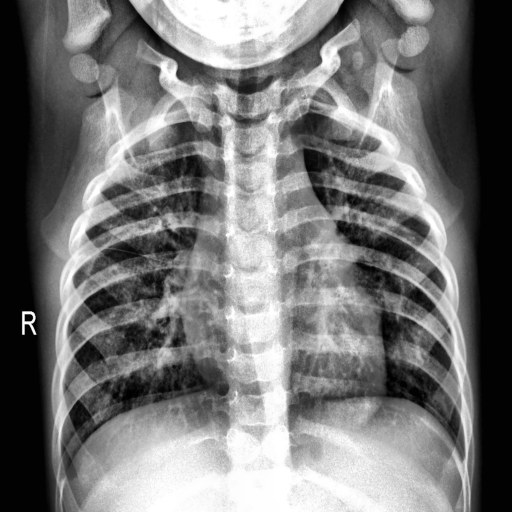

In this work, we only consider the CXR images in a frontal view, namely Poster anterior (PA) and Erect anteroposterior (AP). The first two databases in the above list comprise 520 such images. For the training purpose, we have used these images along with 520 CXR images of normal and pneumonia cases from COVID-19 Radiography Database (Kaggle) COVID19R73:online and Mendeley Chest X-ray Images kermany2018large . Figures 1(a) and 1(b) depicts the manually marked region of interest that distinguishes between COVID-19 and Pneumonia cases in CXR images. The above regions are marked by a radiologist after clinical evaluation of these CXR images.

Figure 8 (a)-(c) shows images relating to COVID-19, Pneumonia, normal cases, respectively. Each subfigure in a row comprises three images of the same patient relating to a medical condition. In each row, the clinical condition has been marked by a radiologist in the first image. In the second image in the same row, the top 10 superpixels obtained using LIME have been marked using green and red colors. Superpixels contributing toward and against the predicted class appear in green and red colors, respectively. Finally, the third image in the same row depicts the LIME-generated heatmap corresponding to the second image. The intensity of the blue color of a particular region in the heatmap corresponds to its relative significance in predicting its class. A radiologist confirmed that in the case of Anteroposterior (AP) chest radiograph (Figure 8(a)), the ill-defined area of ground glass haze in the right lung parenchyma at mid-zone likely represents COVID-19. Similarly, in the Anteroposterior (AP) chest radiograph (Figure 8(b)), the wedge-shaped area of consolidation in the right lung parenchyma at the upper zone likely represents pneumonia. The radiologist confirmed that the regions (though not all) highlighted by LIME correspond to the affected regions in case of both COVID-19 and Pneumonia. This points to the applicability of COV-ELM in the identification of medical conditions such as pneumonia and COVID-19.